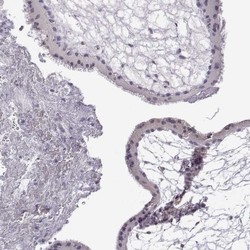

- Immunohistochemistry-Paraffin: VGF Antibody [NBP2-31596] - Staining of human prostate shows no positivity in glandular cells as expected.